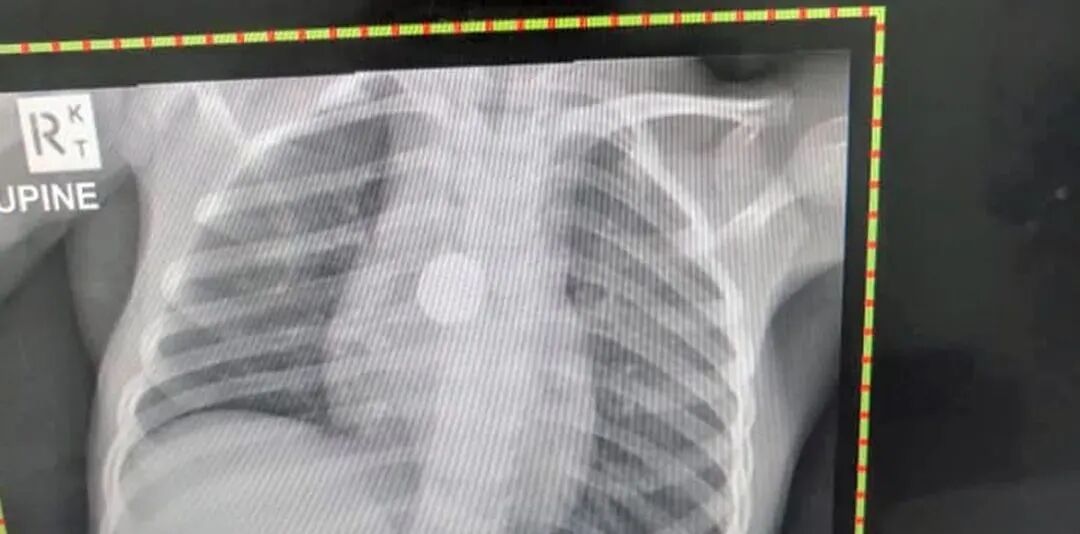

赶到医院的时候,医生发现孩子食管有烧伤,此时已经距离孩子吞下去电池过了大约1小时——

就这短短的一会儿时间,孩子的食道已经被腐蚀烧伤了!

随后,医生给安排了紧急手术,将电池取出...

做完就直接把孩子送进了ICU,即便孩子成功康复出院,还需要戴胃管半个月...